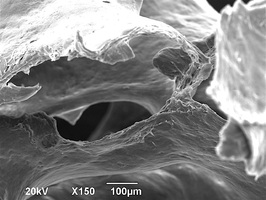

Биоимплантаты аллогенные стерильные губчатые механически и и ультразвуком обработанные.

По внешнему виду представляет собой пористый губчатый блок номинального размера.

2. Поверхность и структура материала для изготовления биоимплантатов